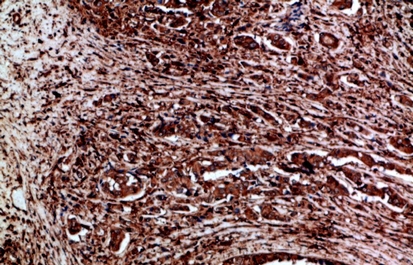

IHC (Immunohistochemisry)

(Immunohistochemistry of paraffin-embedded Human breast cancer tissue using Ret Polyclonal Antibody at dilution of 1:200.)